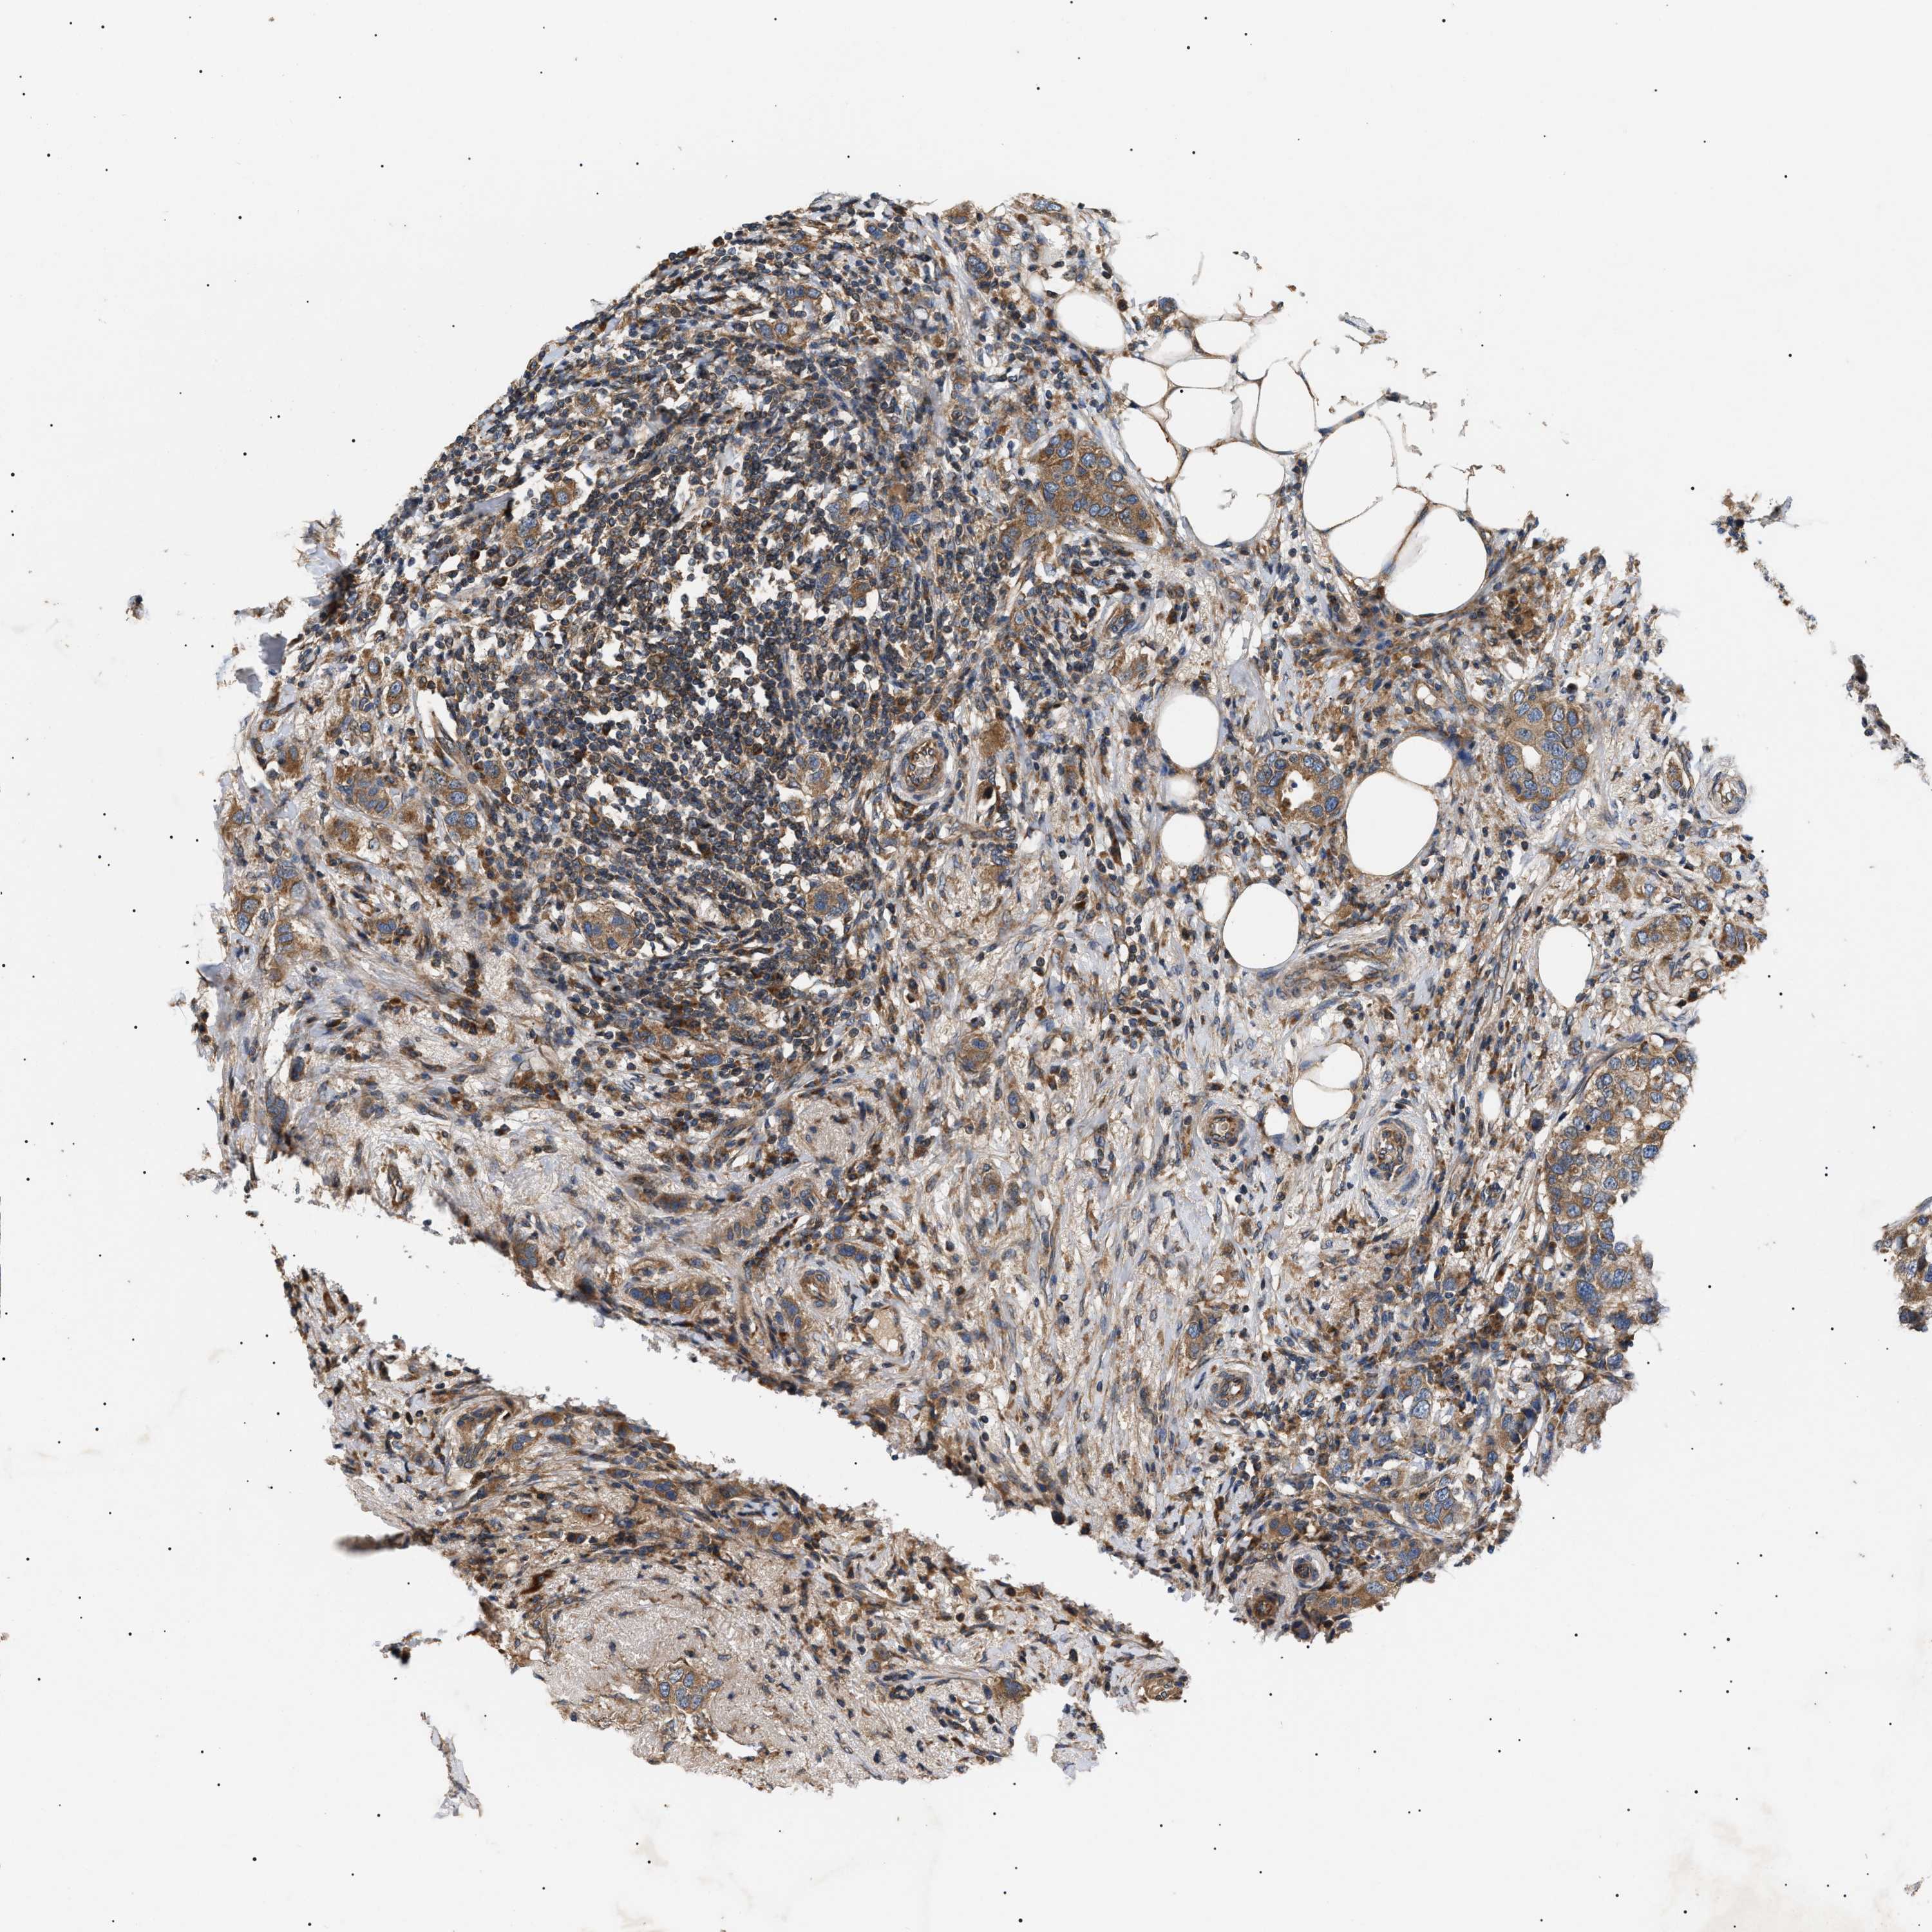

CANCER BREAST CANCER Show tissue menu

BRCA TCGA BRCA VALIDATION PROTEIN EXPRESSION